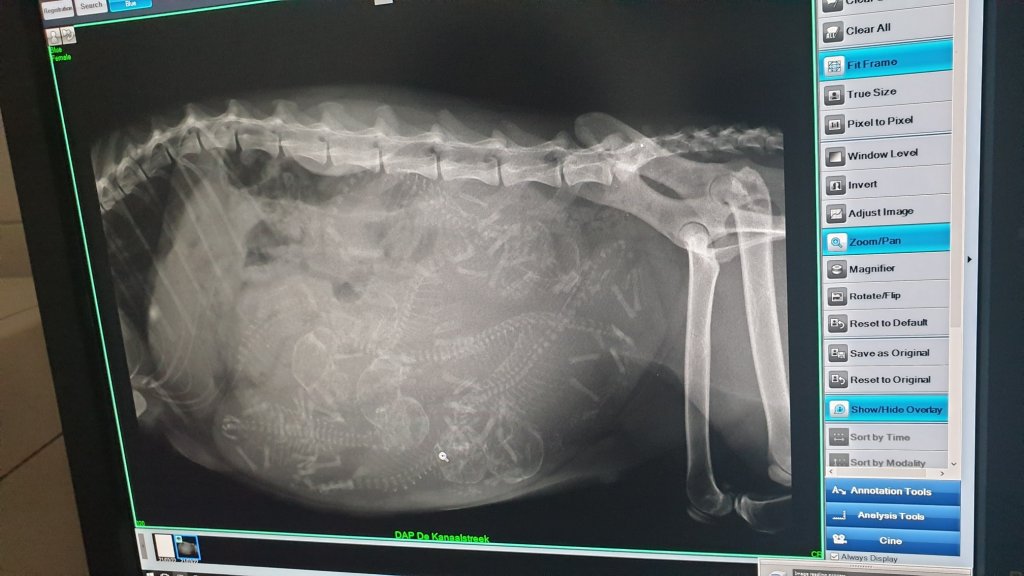

Pawtastic Bresse Blue x Amuletcoon Elvis

Dit jaar is het eindelijk weer tijd om Blue samen te voegen met haar grote liefde Amuletcoon Elvis. Het is aandoenlijk om te zien dat ze elkaar elke dag knuffels geven door de tralies heen. Naast knuffels zijn ze ook constant met elkaar in gesprek. Daar waar Blue in het begin echt een vreselijke hekel aan Elvis had zijn ze nu onafscheidelijk!